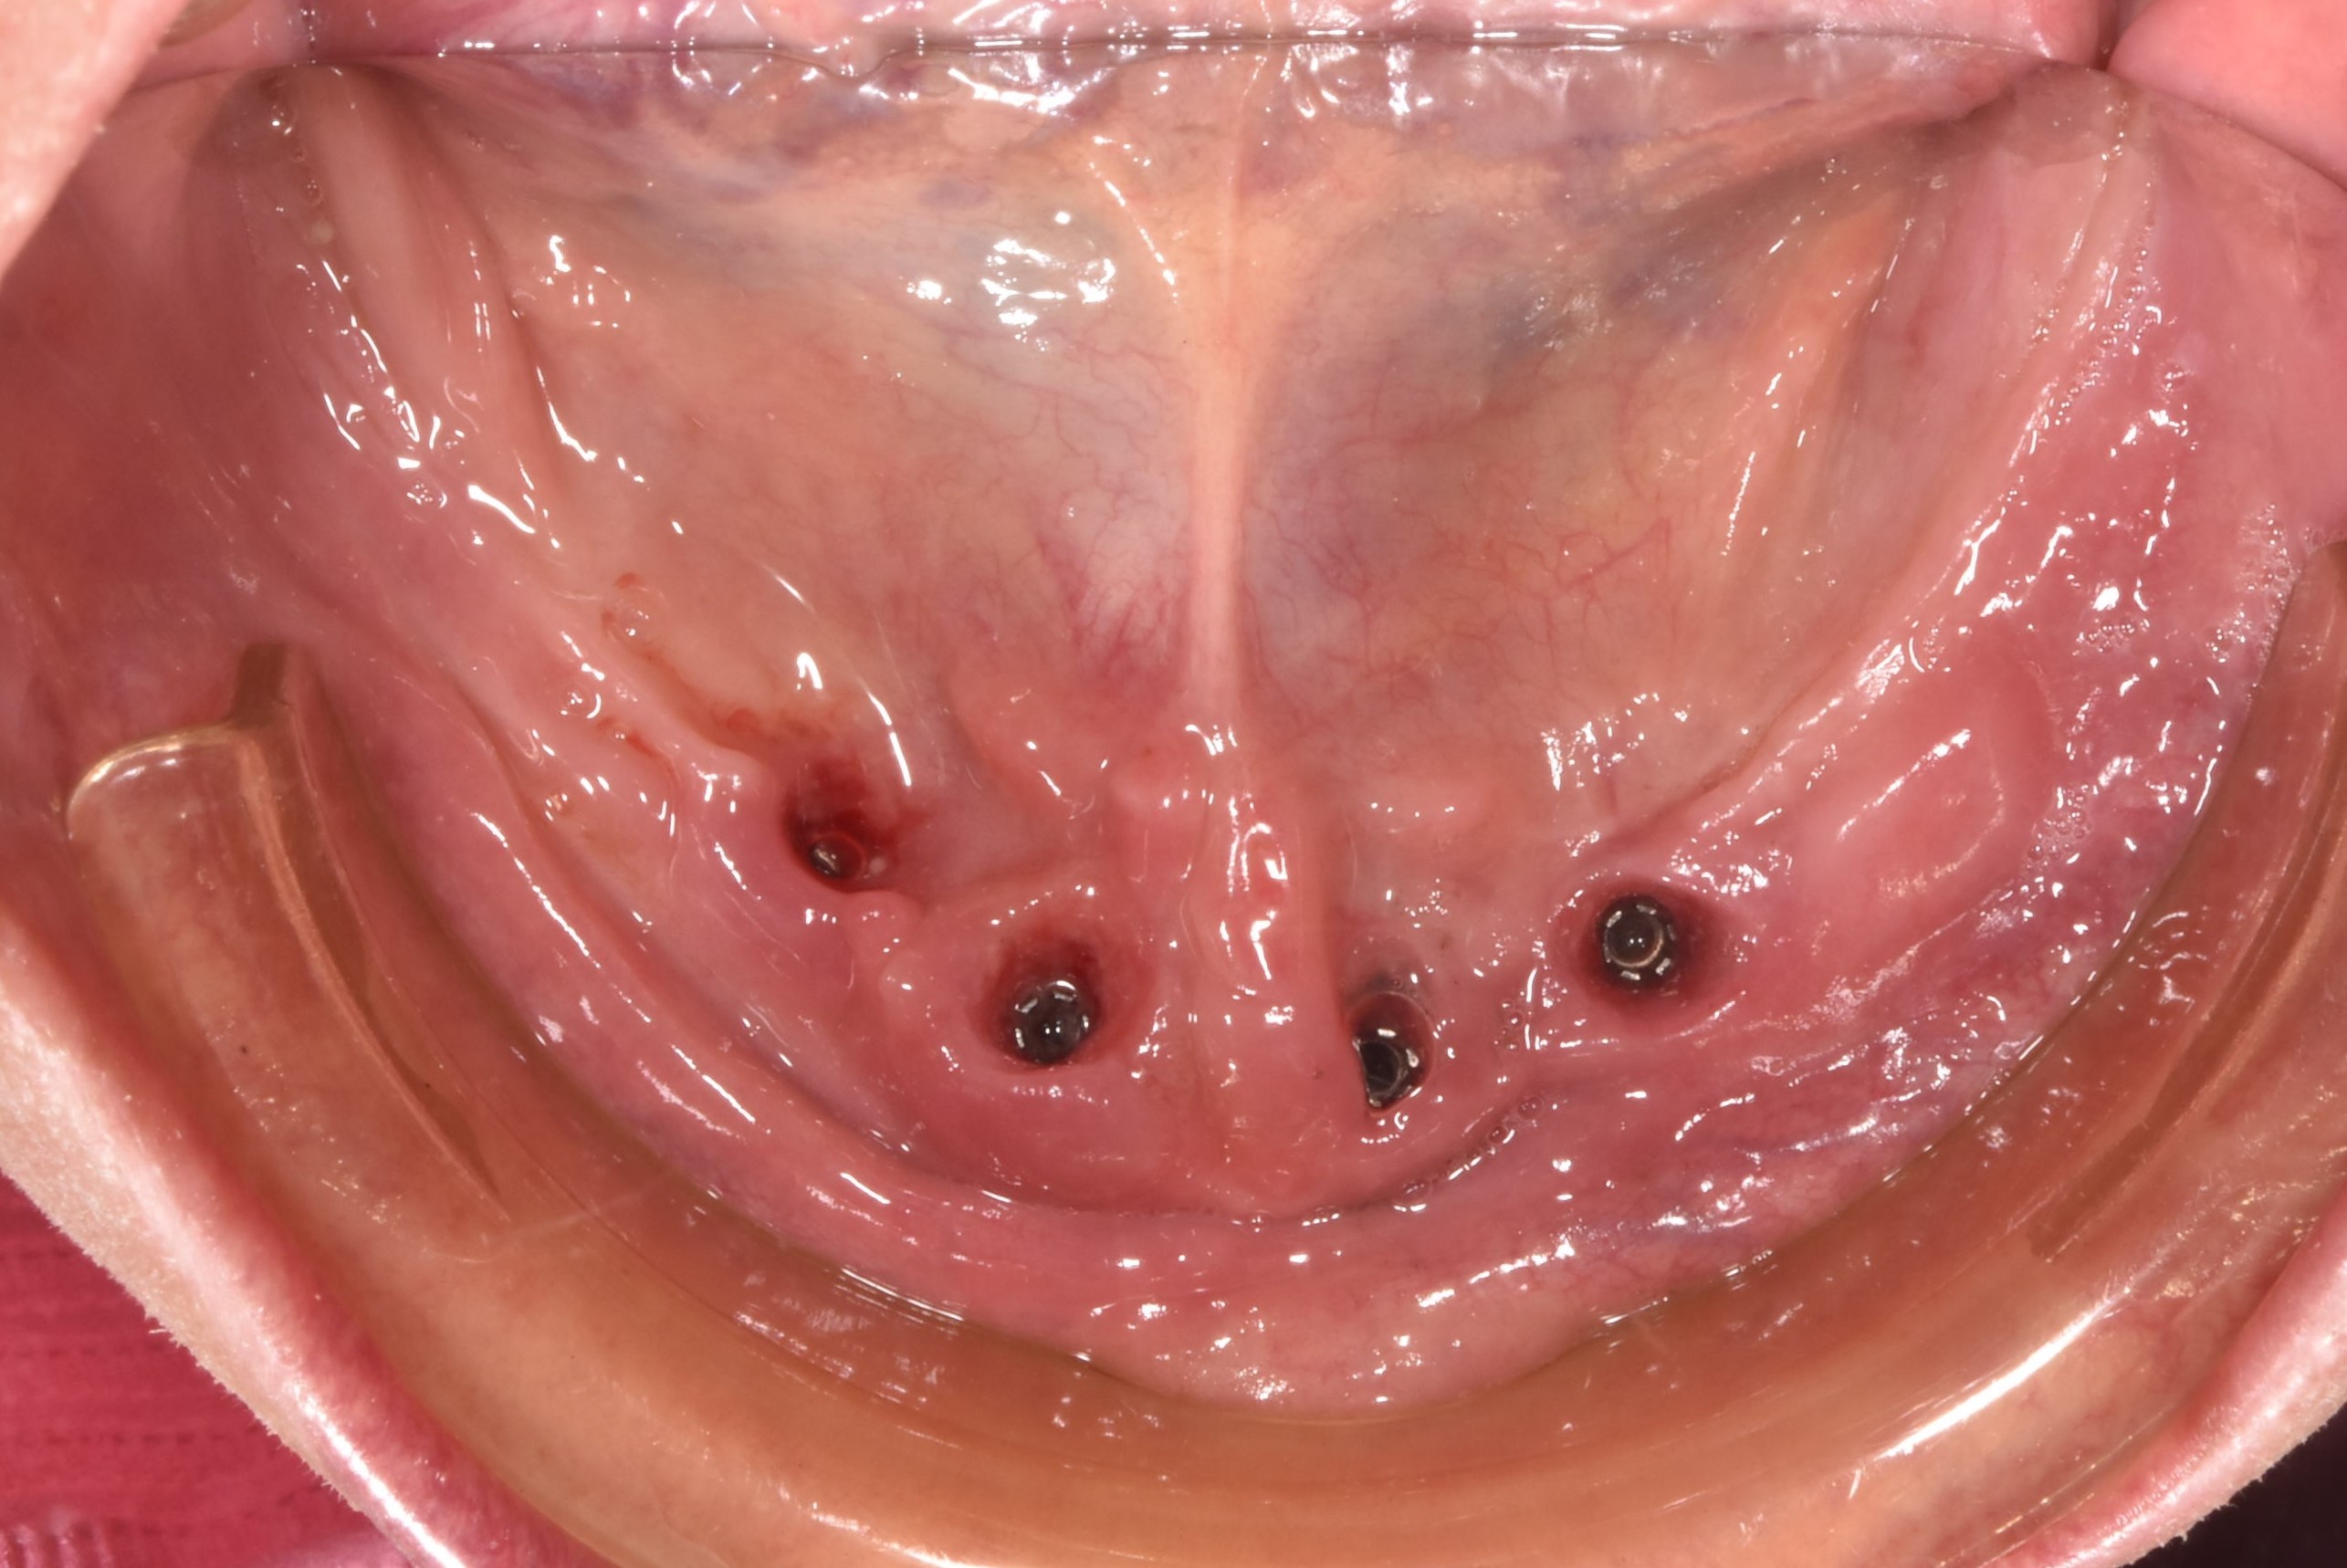

案例二-下顎

醫生透過電腦斷層及全口X光照片評估骨頭狀況決定植入的植體數量、寬度以及深度

大約3-4的癒合時間,把臨時假牙取下並鎖上正式假牙